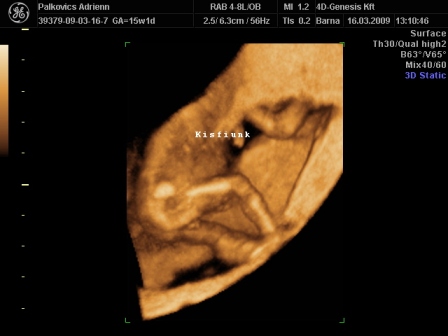

Uh képet is szívesen raknék fel, de hogyis??

Na megpróbálom...